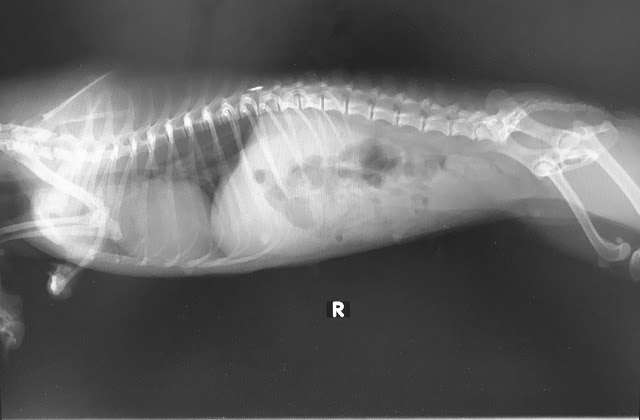

Pippin was given up to Voices for Animals by a breeding farm. As expected, she really wasn’t in the best condition. For starters, Pippin was born with a deformed front limb. Like many other ex-breeding dogs, she was confined to a small area for her entire life despite her deformity. As a result, her spine is curved and her right hind knee is showing signs of luxating patella. In case you’re wondering, reconstruction for her deformed limb is out of the question as her limb is not developed beyond the wrist. Amputation is not required as the limb isn’t being dragged around, nor does it affect her mobility.

We did enquire about getting her a set of wheelies but was advised against it at this point of time as it might possibly hinder her movement. Our priority is to strengthen her muscles to help her better manage her weight distribution. Besides, we actually find it rather endearing how her little limb hangs – kinda like a little big boss.

She also has a real nasty set of teeth – she is missing her front incisors and her canines are fractured. Her rotting teeth also means her breath is out of this world (not in a good way of course). Her kidney readings are slightly off and that is something we will be monitoring in the next few months. Judging from her teeth and appearance, our vet estimated for her to be 8 years old. We later found out from a friend who knew the owner of the farm she came from, that she was actually between 3 and 4 years of age. Her poor condition easily disguised her age, misleading us to think that she was a senior when she is actually just a young budding adult.